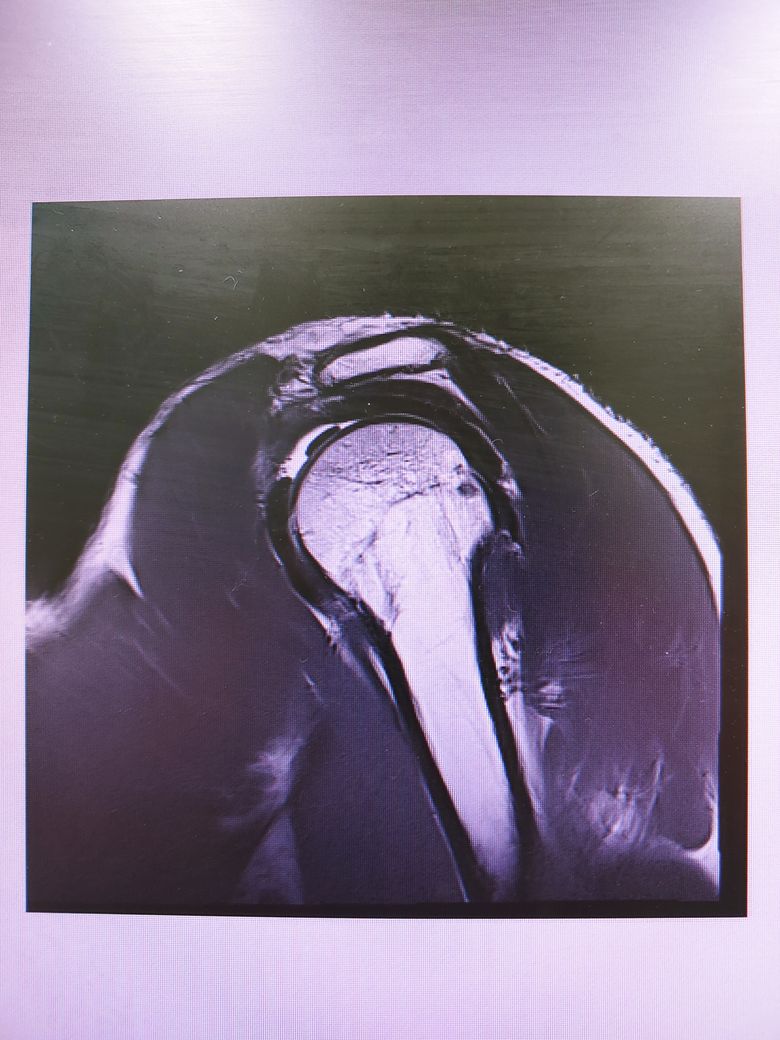

어깨 mri 판독 가능할런지요?

족구 중 다른 사람과 부딛혀 넘어지는데

상대가 넘어지지 말라고 팔을 잡아주었습니다.

그런데 무방비 상태에서 팔이 당기다보니

어깨에서 소리가나더라구요.

세달째 통증이 지속되어

병원가서 Mri는 찍고 아직 진단은 받지 못했습니다..

회전근개 부분파열으로 볼 수 있나요..?

어깨 MRI는 수십장 이상의 사진이 연속적으로 찍히는 것으로 위 사진들만으로는 정확한 판별이 어렵겠습니다.

나와있는 cut에는 큰 문제가 없어보입니다.

현재 사진상으로 회전근개 파열을 확실히 진단하기는 힘들것 같습니다.

하지만 현재 MRI상 어깨 관절내에 밝게 보이는 곳은 물 또는 혈액등으로, 활액막염 등으로 인해 염증성 변화가 일어난 것으로 보입니다.

이는 소염진통제 등을 드시면서 경과관찰을 해보시는 것이 좋겠으며, 현재 사진만으로는 회전근개 파열을 단정하기 어려우므로 정확한 진단에 대해서는 해당병원에서 설명을 들으시는 것이 좋겠습니다.